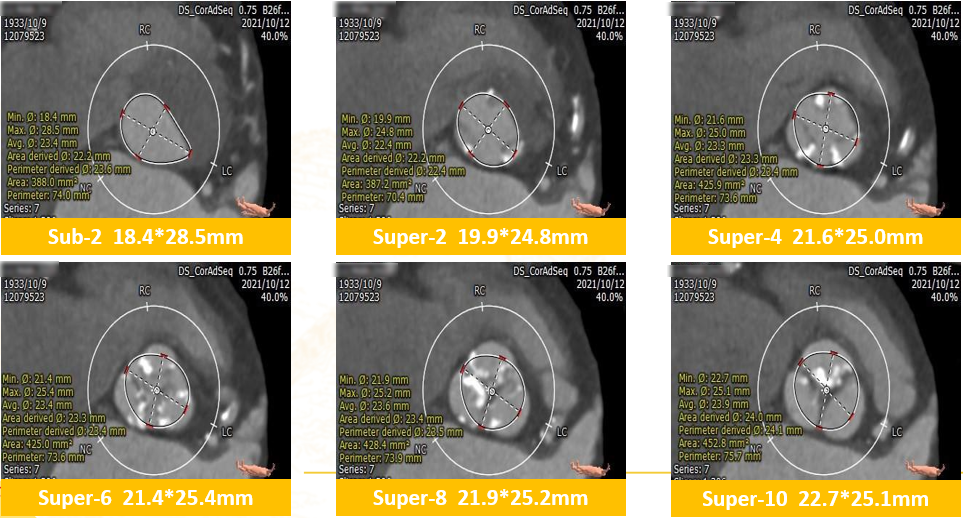

CT评估:三叶瓣,小瓣环,窦部较小,钙化不重,左室心腔小,冠脉高度可,双下肢入路可。

2. 多平面测量CT评估

瓣膜选择:植入23mm TaurusElite瓣膜